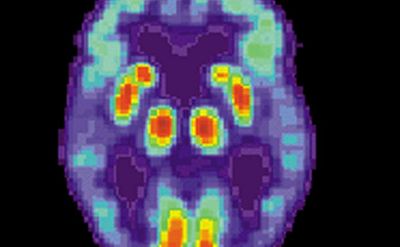

2018年8月1日 讯 /生物谷BIOON/ --美国境内有570万人患有阿兹海默症,而目前仍然没有有效的,针对这种疾病的治疗以及预防方法。不过,精准医疗或许能够为治疗阿兹海默症提供一些新的思路。

最近,相关领域的研究者们发现两种实验性的药物:“BAN2401”以及“Anavex2-73”,或许具有治疗上述疾病的效果。

在关于BAN2401的临床试验中,研究者们招募了856名早期阿兹海默症患者。结果表明:在接受了长达18个月的治疗之后,接受最高剂量的患者组出现了明显的淀粉样斑块降低的现象。此外,相比对照组患者,实验组的临床症状缓解比例达到26%。

另外一项临床试验中,研究者们在小规模的患者群体中验证了Anavex 2-73能够降低甚至扭转早期的认知下降症状。此外,作者通过对患者体内的33000多个还基因进行筛查与比较,发现患者基因组中的某些基因差异会影响该药物的作用效果。这一结果表明,对于某一类药物而言,可能只针对特定类群患者有效。这也再次强调了精准医疗在治疗阿兹海默症等神经退行性疾病中的意义。